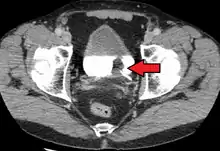

The most common sites for bladder cancer metastases are the lymph nodes, bones, lung, liver, and peritoneum.[78] The most common sentinel lymph nodes draining bladder cancer are obturator and internal iliac lymph nodes. The location of lymphatic spread depends on the location of the tumors. Tumors on the superolateral bladder wall spread to external iliac lymph nodes. Tumors on the neck, anterior wall and fundus spread commonly to the internal iliac lymph nodes.[79] From the regional lymph nodes (i.e. obturator, internal and external lymph nodes) the cancer spreads to distant sites like the common iliac lymph nodes and paraaortic lymph nodes.[80] Skipped lymph node lesions are not seen in bladder cancer.[79]